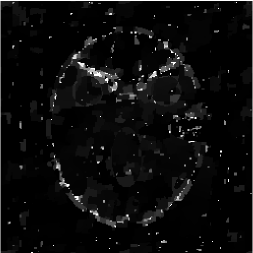

Figures 4 and 5 present visual reconstruction results of the SL phantom and the FB phantom, respectively, both under high additive Gaussian noise (). In particular, Figure 4 is to recover the SL phantom using 7 radial lines. The model has severe streaking artifacts due to this extremely small number of data obtained on the radial lines. The minimization on the gradient yields significant improvements over the baseline model (TV). The proposed algorithm outperforms the previous ADMM approach at the outer ring and boundaries of the three middle oval shapes, which are more obvious in the difference map to the ground truth. On the other hand, the FB phantom has finer structures and lower image contrast compared to the SL phantom. As a result, it requires 13 radial lines for a reasonable reconstruction. As we observe in Figure 5, the overall geometric shapes are preserved. At the same time, many speckle artifacts appear in the reconstructed images by no matter which algorithm is used.